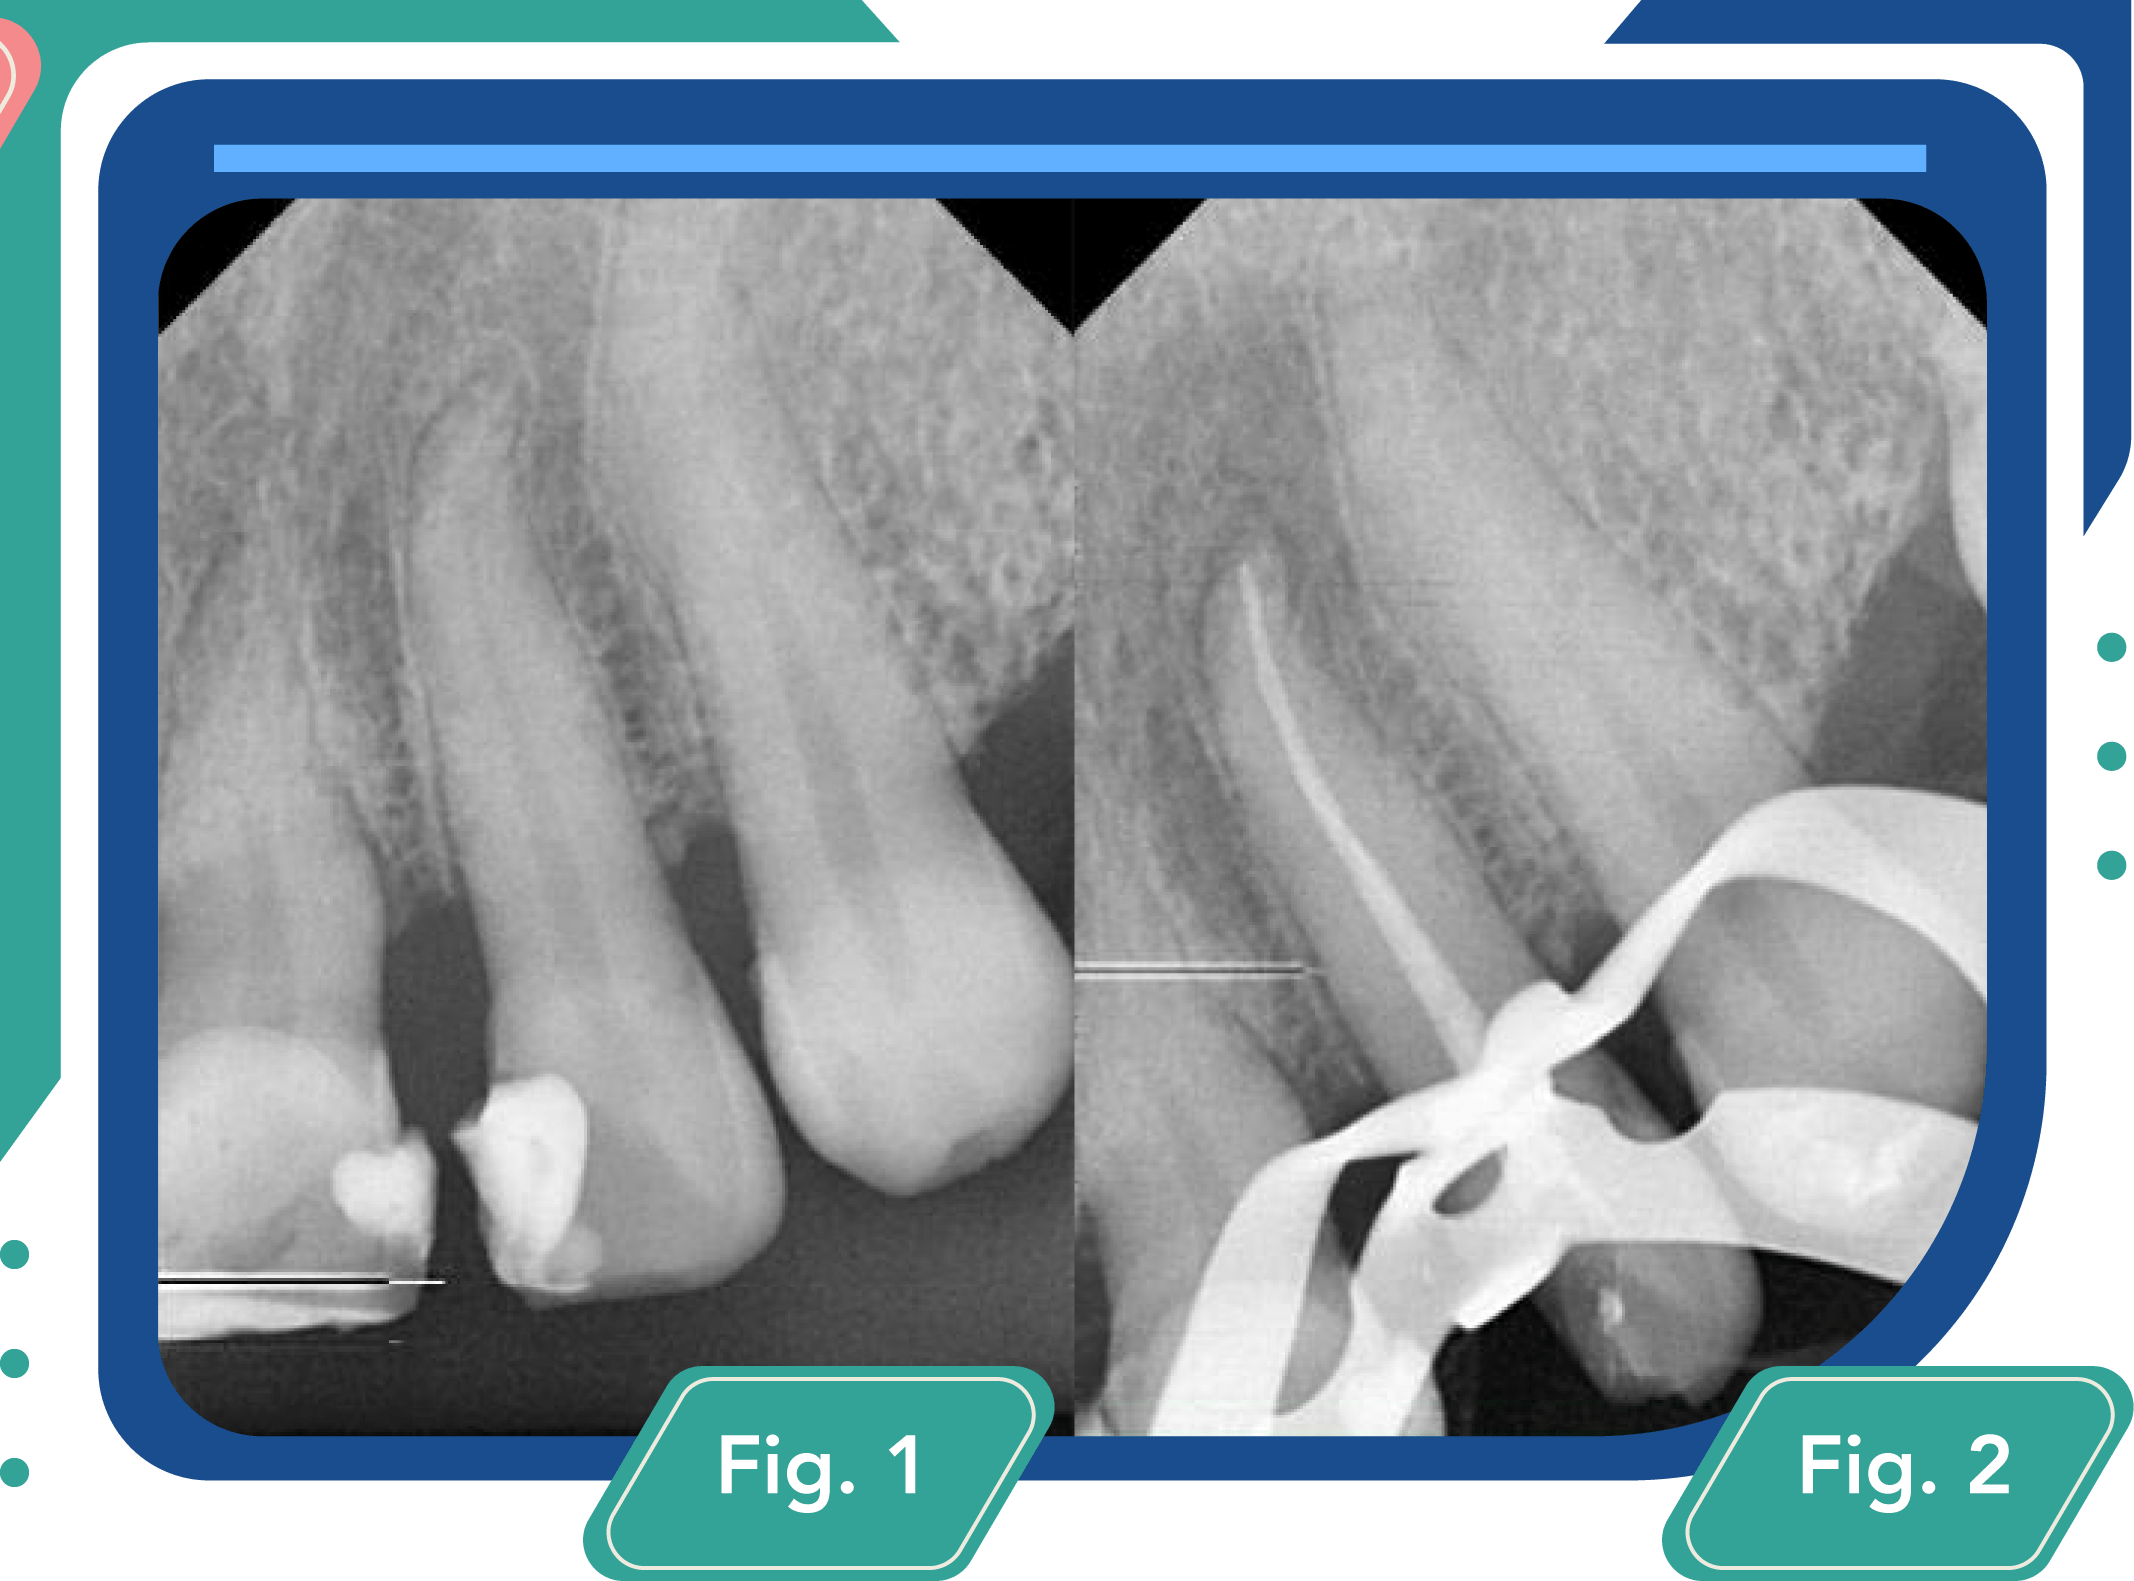

Al hacer la remoción de la restauración defectuosa y la caries activa se comunica con la cámara pulpar, optando por adaptar la apertura a través de la cavidad ya existente (con el fin de conservar el sustrato dental) y realizar el tratamiento endodóntico Fig. 2